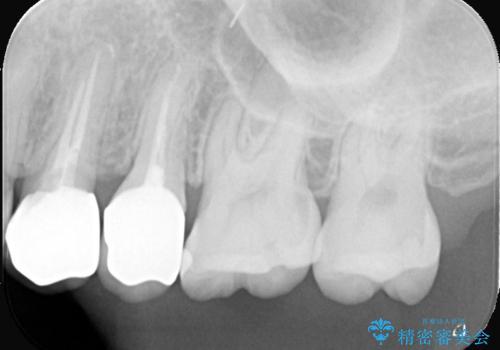

- 「銀歯があるとお口の中が気持ち悪い感じがするので、セラミックに変えたい」を主訴に来院された患者様です。

銀歯と虫歯を除去し、オールセラミッククラウンで治療を行いました。

銀歯の下は虫歯になっていました。 根管治療は希望されなかったため、虫歯を除去後、被せ物のみオールセラミックで治療を行いました。